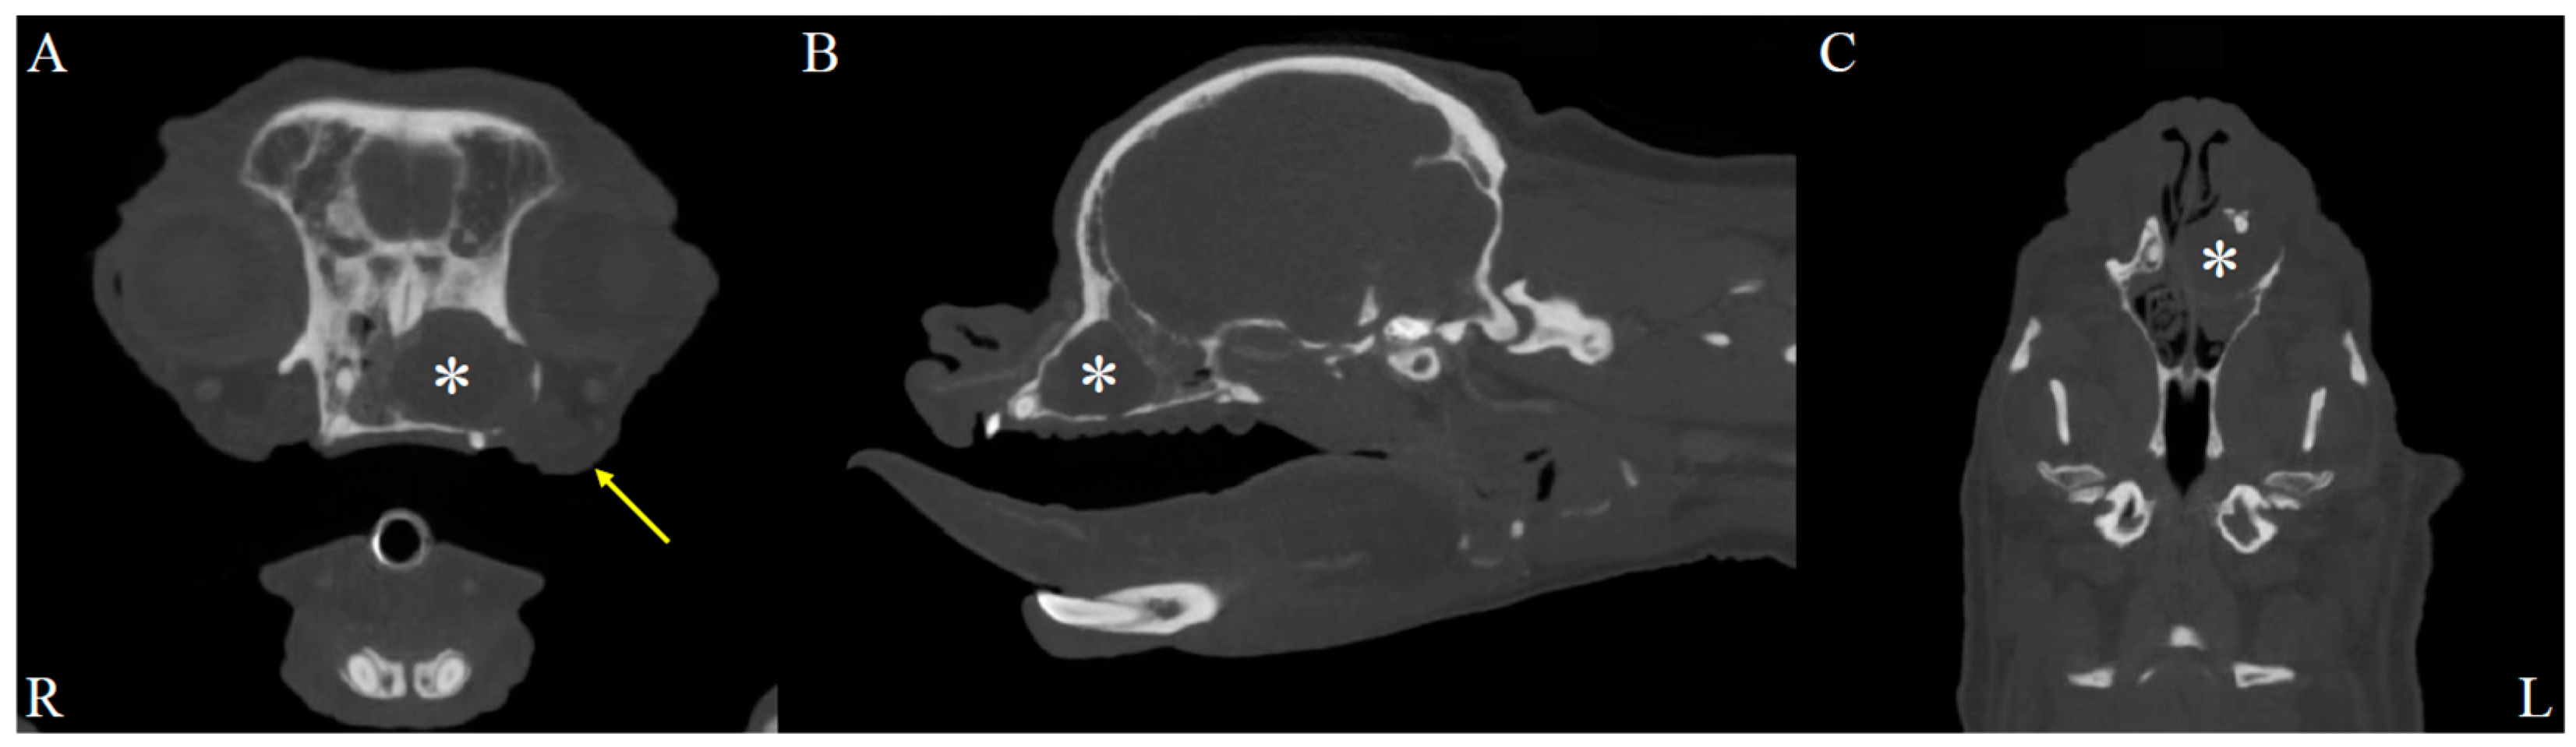

On physical examination, the dog showed serous nasal discharge in the left nasal cavity, nasal congestion, and intermittent reverse sneezing. Other physical examinations were unremarkable. Based on these findings, further computed tomographic (CT) evaluation of the nasal cavity was required. The dog was premedicated with butorphanol (0.2 mg/kg, intramuscular injection, Myungmoon, Seoul, Republic of Korea). Anesthesia was induced with propofol (6 mg/kg, intravenous injection, Myungmoon, Seoul, Republic of Korea). Intubation was performed, and anesthesia was maintained with isoflurane. CT (MyVet CT i3D, Woorien, Seoul, Republic of Korea) images of the nasal cavity were obtained. CT findings revealed a fluid-attenuated structure measuring 1.35 × 1.68 × 1.49 cm located in the mid-region of the left nasal cavity. The lesion involved the left nasal cavity, accompanied by soft tissue swelling in the adjacent left perinasal region, suggesting possible pathology in both the nasal cavity and surrounding soft tissues (Figure 1). The scan also revealed a fluid-attenuated mass occupying the nasal cavity, with evident contrast enhancement in the adjacent soft tissues, indicating pathological involvement of the surrounding structures (Figure 2).

Figure 1. Soft tissue window, post-contrast CT images of the dog’s head. Axial (A), sagittal (B), and dorsal (C) post-contrast CT images in the soft tissue window reveal a lesion in the left nasal cavity (R: right, L: left). A fluid-attenuated structure (asterisks) measuring 1.35 cm in height, 1.68 cm in width, and 1.49 cm in length is observed in the mid-region of the left nasal cavity. Additionally, soft tissue swelling is evident in the left perinasal region (yellow arrow), suggesting involvement of adjacent soft tissues.